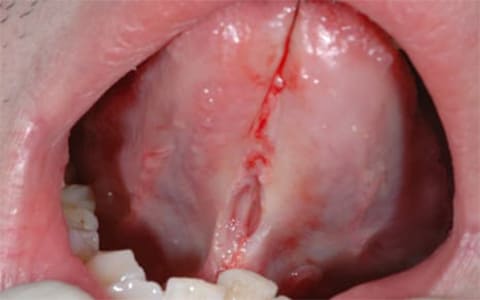

STEP.03

舌を糸で牽引して舌小帯にメスを入れて切開する -

STEP.04

切るという感じではなくメスを当てることで切開部が広がっていく感じである